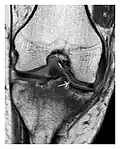

Figure 1: A 56-year-old woman presenting with left knee pain after a fall. (a) Initial anteroposterior radiograph was considered normal, however, subtle cortical disruption of the anterior rim of the medial tibial plateau, medial to the tibial spine, is noted (arrow). (b) Coronal T1-weighted MRI confirms the cortical disruption (arrow) and shows extensive fracture through the proximal tibia. (c) Coronal proton density-weighted image with fat saturation shows extensive edema in the subchondral bone. Note also hypersignal adjacent to the medial collateral ligament corresponding to a grade I sprain (arrowheads).[1]

Figure 8: Proximal diaphyseal fatigue fracture of the tibia in a 20-year-old man with a history of regular jogging. (a) Lateral radiograph shows no obvious fracture lines but a subtle localized medial tibial cortex periosteal reaction (arrows). (b) Sagittal reformatted CT image acquired 1-month after the radiograph shows a linear hypoattenuation in the tibial cortex (arrowhead), as well as obvious periosteal thickening (arrows). (c) Sagittal T2-weighted fat-saturated image acquired the same day shows an area of hyperintensity spreading over the proximal tibia (arrows), which is consistent with the presence of proximal tibial fracture.[1]